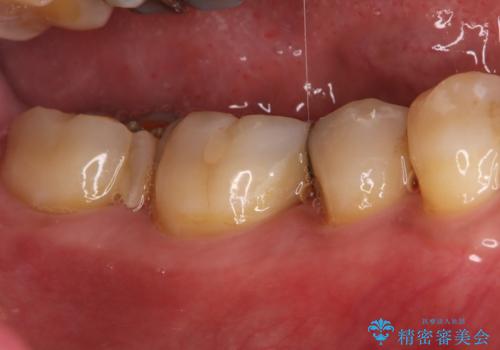

- 以前治療した右下7番(奥歯)のインレー(詰め物)が欠けてしまったことを主訴にご来院されました。診査の結果、残っている歯質が少なく、通常の詰め物では再び歯が割れてしまう破折リスクが高いと診断しました。このリスクを回避し、強い咬合力に耐えられるよう、歯全体を覆うクラウン(被せ物)による修復を提案。素材には、強度と適合性に優れたPGA(白金加金)クラウンを選択し、長期的に安定した奥歯の機能回復を目指しました。